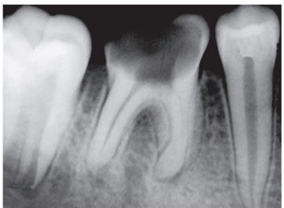

Observe a imagem abaixo, onde o elemento dentário em questão apresenta-se com Necrose Pulpar com Periodontite Apical Aguda.

Marque a alternativa que descreve corretamente as características da necrose pulpar com periodontite apical aguda.